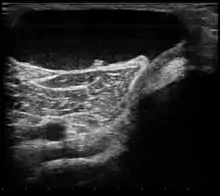

| Ultrasound image of Baker's cyst | |

| Diagnostic method | Confirmed by ultrasound or MRI[3] |

Diagnosis is by examination. A Baker's cyst is easier to see from behind with the patient standing with knees fully extended. It is most easily palpated (felt) with the knee partially flexed. Diagnosis is confirmed by ultrasonography, although if needed and there is no suspicion of a popliteal artery aneurysm then aspiration of synovial fluid from the cyst may be undertaken with care. An MRI image can reveal presence of a Baker's cyst.